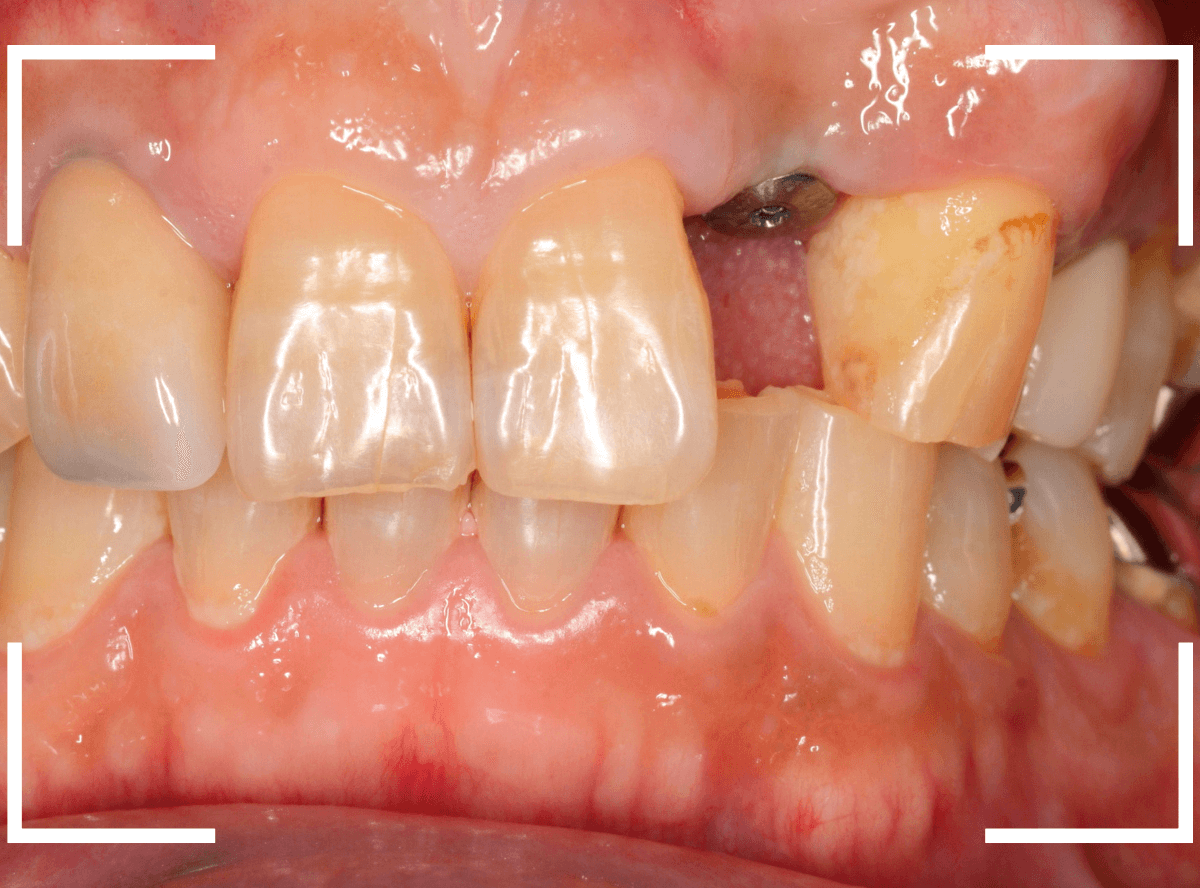

インプラントset後の状況です。

審美的にも、満足いただける仕上がりになりましたが、現在の状況を維持するために治療後の定期メンテナンスが不可欠になります(インプラントに限りませんが)。

| 治療回数 | 8回 |

| 治療期間 | 約半年 |

| 費用 | 30万円(レントゲン検査代、消費税含む) |